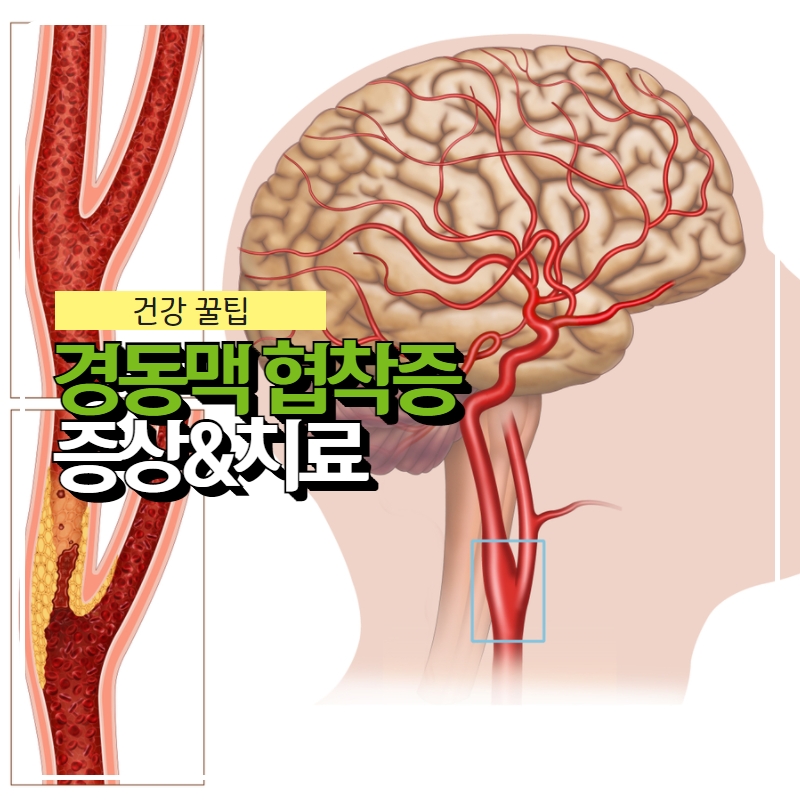

경동맥이 막히는 질환을 ‘경동맥협착증’이라고 합니다. 허혈성 뇌졸중 원인의 30%를 차지할 정도로 우리 생활에 바짝 다가선 경동맥협착증.

경동맥 협착증의 증상